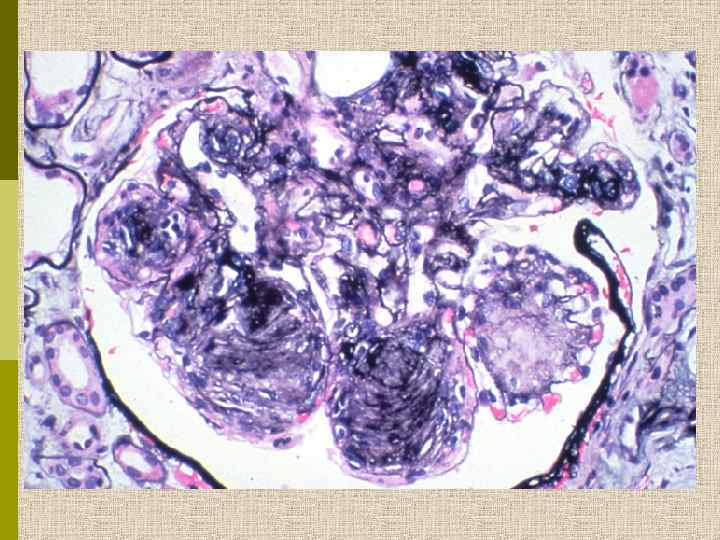

МОРФОЛОГИЧЕСКИЕ ИЗМЕНЕНИЯ ПРИ ДИАБЕТИЧЕСКОЙ НЕФРОПАТИИ Основные варианты - диабетический гломерулосклероз с узелками Kimmelstiel-Wilson - диффузный мезангиальный гломерулосклероз Характерные признаки Утолщение ГБМ; артериолярный гиалиноз; аневризматические капилляры; капсулярные капли; фибриновые шапочки; атрофия канальцев; инфильтрация, расширение и склероз интерстиция; линейные отложения иммуноглобулинов

У БОЛЬНЫХ САХАРНЫМ ДИАБЕТОМ ГЛОМЕРУЛОНЕФРИТ ВСТРЕЧАЕТСЯ В 4 РАЗА ЧАЩЕ, ЧЕМ У ЗДОРОВЫХ ЛЮДЕЙ Результаты нефробиопсии у 132 больных (из общего числа 6000 больных) сахарным диабетом (Parsons V. , NDT, 1994, 9, 848; London) В дополнение к диабетическому гломерулосклерозу, гипертензивным и атеросклеротическим изменениям, или пиелонефриту, гломерулопатия выявлена у 37 больных (27%) 11 больных - Ig. А гломерулонефрит (преимущественно при ИЗСД) 9 - пролиферативный ГН с полулуниями 6 - амилоидоз или отложения легких цепей (в основном у пожилых) 4 - васкулит 3 - мембранозная нефропатия 2 - ФСГС 1 - минимальный гломерулонефрит с лимфолейкемией 1 - смешанная криоглобулинемия